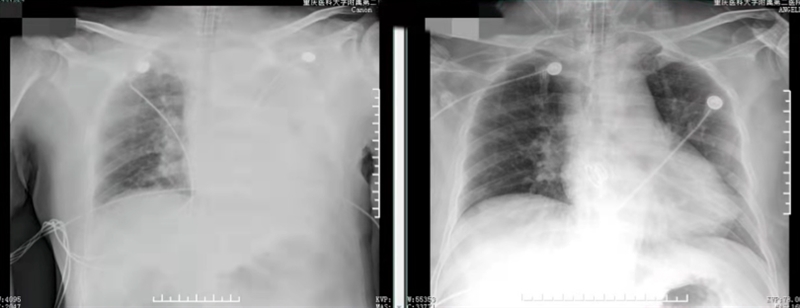

因患者的气道异物较大且多,急诊纤支镜仅能吸出部分异物,经过两小时艰难抢救,患者生命体征虽暂趋平稳,但解除气道梗阻亟需解决。紧接着,呼吸内科接过抢救的接力棒,吴先生被转至呼吸内科行支气管镜冷冻治疗,镜下再次取出较多异物,床旁胸片提示患者左肺恢复透亮,至此,吴先生的气道梗阻终于得以解除,医护人员们总算将他从“鬼门关”抢了回来。

( 急救后,胸片对比)